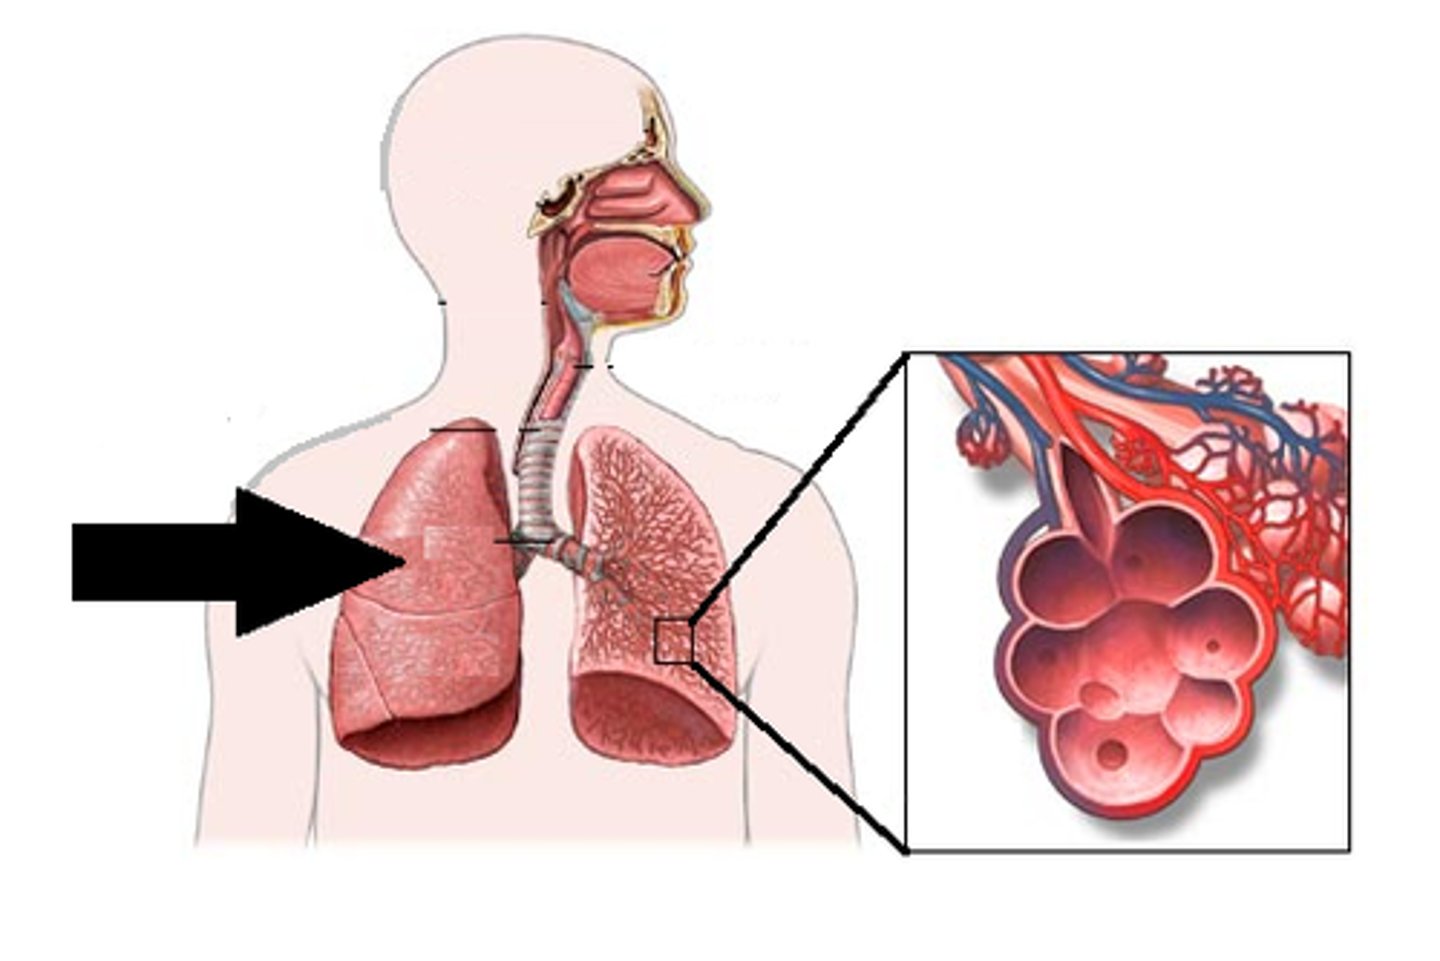

lung

organ of the respiratory system that performs gas exchange

alveoli

tiny sacs of lung tissue specialized for the movement of gases between air and blood